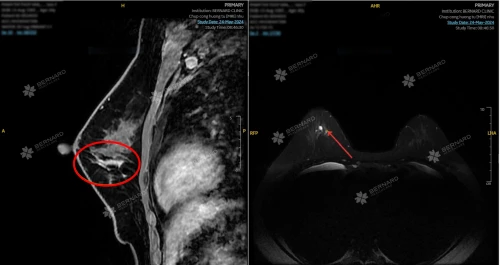

- Chụp cộng hưởng từ (MRI) tuyến vú động học có tiêm tương phản

Giúp phát hiện sớm ung thư vú; Bệnh lành tính do đặt túi như bao xơ co thắt, rò rỉ túi, BIA-ALCL (lymphoma liên quan túi ngực); Tình trạng viêm - tự miễn liên quan đến túi ngực nhám (theo cảnh báo của FDA Hoa Kỳ).